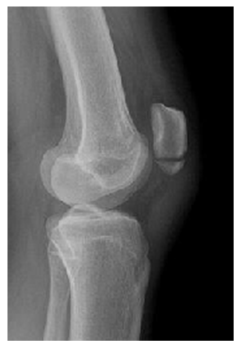

We report a case of a 15 year old female who sustained a left side transverse distal patella fracture (Figure 1) while participating in tack and field upon landing after long-jump.  After a thorough discussion of non-operative verses operative treatment, the patient and her parents elected to move forward with fixation of the fracture to promote healing, allow early mobilization and minimize the risk of displacement. Because of minimal displacement, it was elected to move forward with a previously described suture tension band technique using #5 FiberWire.10 The unique aspect of this case is the percutaneous placement of this figure-of-8, tension band suture fixation (Figure 2).

Four small incisions were made, each measuring 3-5mm. Two on either side of the proximal patella tendon or two more on either side of the distal quadriceps tendon. Labeled 1-4 (Figure 2). A large straight Keith needle was used to pass the suture starting from point 1 to 2, through the patella tendon at the inferior pole of the patella (Figure 3). The free suture end from point 2 is subcutaneously retrieved to point 3 with a Hewson suture passer (Smith and Nephew, Andover MA) (Figure 4). This free end of this suture is then passed from point 3 to 4 is with a straight Keith needle, through the quadriceps tendon at the superior pole of the patella. Finally, the other free suture end is retrieved from point 1 and delivered to point 4 (Figure 5). The free suture ends are then tensioned and tied at point 4 (Figure 6), completing the figure-of-8 tension band. A small tenotomy scissor was placed into each of the four incisions freeing the bursa from the tension band suture. Once all skin adhesions were clearly released, the four small incisions were closed, each with a single nylon suture.

Figure 2 Diagram demonstrating percutaneous tension band suture technique. Numbers 1-4 represent the sequential placement of the sutures. A straight Keith needle is used to place the suture from point 1 to 2, through the patella tendon. The free suture end from point 2 is subcutaneously delivered to point 3 with a Hewson suture passer. The suture from point 3 is delivered to point 4 with a straight Keith needle, through the quadriceps tendon. Finally, the free suture from point 1 is delivered to point 4, subcutaneously with a Hewson suture. The free suture ends are tensioned and then tied at point 4.